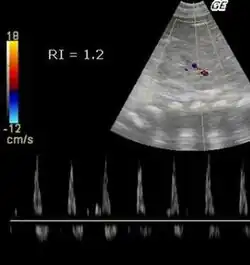

| 1 | Систолический кровоток, диастолический кровоток отсутствует |

| >1 | Обратный ток крови во время диастолы |

После трансплантации почки у пациентов с RI> 0,8 наблюдается повышенная смертность.